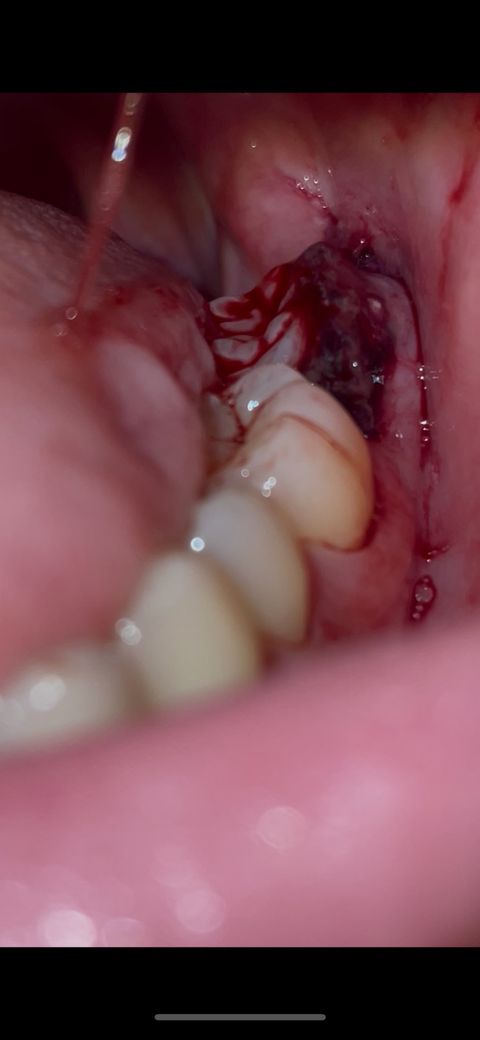

매복사랑니 발치 2일차인데 혈병이 내려온거 같아요

첫날에는 거의 안아팠는데 2일차 저녁에 이렇게 혈병이 앞으로 나와있고 턱도 뻐근합니다ㅜ 씹히기도 해요. 문제 있는걸까요? 낮에 치과에서 소독해주실땐 별 말씀 없으셨어요

그리고 내려온 혈병은 그대로 두면 되는걸까요?

발치한지 이틀이 지나도 저정도로 피가 난다면 지혈이 잘 안되거 같으니 치과에 가셔서 소독을 한번더 받아보세요.

발치 부위를 벗어난 피떡은 치유에 큰 도움은 안됩니다. 자연스럽게 제거된다면 그래도 괜찮지만 일부러 떼어내거나 하진 마세요

턱이 뻐근한 건 발치하는 동안 턱을 오래 벌리고 있어서 그럴 가능성이 높습니다 냉찜질과 온찜질 번갈아가면서 해주세요